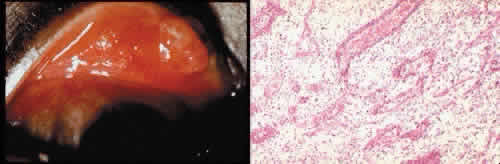

that results in reestablishment of functional ocular anatomy.1–3 The goal of therapeutic intervention in the setting of ocular trauma is to promote the repair process and to allow it to proceed as rapidly as possible and heal as completely as possible without compromising ocular function.4 CELLULAR AND EXTRACELLULAR COMPONENTS The four basic cell types found in wound healing are fibroblasts, vascular endothelial cells, inflammatory cells, and epithelial cells. Specialized cell types that participate in ocular wound healing include corneal endothelial cells, retinal pigment epithelial cells, and Müller cells of the retina. Specific cell populations enter an area of injury under the influence of complex biochemical and biophysical processes involving proteins of the extracellular matrix and the coagulation system. Intracellular proteins, such as tubulin and actin, andmyosin filaments function in cell locomotion. Extracellular matrix proteins, such as fibronectin, laminin, and type IV collagen, orient and regulate cell migration and adhesion.5 Coagulation proteins, such as von Willebrand's factor and plasminogen, alsofunction in regulating the cellular events of healing. Vascular endothelial cells are stimulated to leave their resting state and digest basement membrane, proliferate, migrate, and eventually differentiate under the direction of multiple angiogenic growth factors.6 A wound usually is filled first by a fibrin coagulum. Neutrophils, lymphocytes, and histiocytes (macrophages) enter the wound through fibrin scaffolding to clear necrotic debris and confine toxic or foreign substances. Granulation tissue often is the first type of reparative tissue in wound healing (Fig. 1). Although its composition varies somewhat, small-caliber vascular channels in a delicate collagenous stroma infiltrated by acute and chronic inflammatory cells generally characterize it. This amorphous tissue serves as a template for more definitive repair. Metaplasia is the transformation of a cell from one adult cell phenotype to a second cell phenotype. In advanced wound healing, fibroblasts acquire intracytoplasmic characteristics of smooth muscle cells (myofibroblasts).7 The myofibroblasts are able to contract and bring wound edges together. Vascular endothelial cells proliferate and migrate into the wound from preexisting adjacent vessels. The new “vessel” migrates initially as a solid bulb of endothelial cells. This solid cord of cells will canalize and differentiate into mature arterioles, venules, and capillaries. Fibroblasts grow into the wound in a radial manner but will eventually reorient and secrete collagen along lines of established tissue tension. Epithelial cells are found covering surfaces of tissue. Two distinct types of epithelial cells cover the ocular surface: corneal epithelial cells and conjunctival epithelial cells. Cell replacement is accomplished by stem cells located at the limbus for the corneal epithelium8,9 and at the mucocutaneous junction and possibly throughout the conjunctiva for the conjunctival epithelium.10 Migration and proliferation of surrounding healthy epithelial cells heal surface discontinuity. Apoptosis is a biochemical process leading to programmed cell death. Cell death in apoptosis results from intracellular messages. In necrosis, cell death results from toxic external factors (e.g., hyperosmolality). Apoptosis allows for elimination of entire populations of cells without tissue damage or an inflammatory response.11 Elimination of certain cells is advantageous in embryology (e.g., when scaffolding structures are no longer necessary as with the primary vitreous). In certain neoplastic conditions, however, defects in apoptosis may lead to disadvantageous accumulation of cells. Apoptosis also seems to be highly influential in all types of inflammation, including wound healing. In wound healing, apoptosis may function to control the type and degree of tissue response.12 In the anterior cornea, keratocytes have been observed to undergo apoptosis in response to wounding of the cornea.13,14 Abnormalities of apoptosis may be responsible for such conditions as keloid formation in the skin15 and keratoconus in the cornea.16 Wound healing of highly specialized tissues of the eye has several unique features. CORNEAL HEALING The healing of the cornea is unique relative to other soft tissues, because it lacks blood vessels and because it is lined anteriorly and posteriorly by layers of epithelial-like cells. Epithelial cells of the corneacan produce essential wound healing factors normally produced by platelets.17 Architectural repair is accomplished at the level of the corneal stroma. Abrasions are injuries generally involving only the superficial layer (epithelium) of the cornea (Fig. 2). Abrasions are commonly caused by mechanical injuries or anoxia resulting from contact lens overwear. Some or all of the layers of the surface epithelium are lost, but Bowman's membrane remains intact. After a delay of approximately 1 hour, uninjured epithelial cells at the margin of the wound loosen their intercellular and basal attachments and migrate en masse toward the injured area.18 The shape of the wound margin and the biochemical characteristics of the exposed tissue influence the direction and extent of the migration.19 If the entire corneal epithelium is abraded, migrating epithelial cells derived from the limbal stem cells are able to cover the defect completely within 48 to 72 hours. The epithelium will be much thinner than normal until mitotic division reestablishes normal thickness. Re-formation of epithelial basement membrane may not be detectable for as long as 6 weeks after injury.20 Clinically, the healed wound is transparent. Small defects of Bowman's membrane (Fig. 3) do not heal by fibrous proliferation of the stroma. The defect is filled by proliferating epithelial cells (epithelial facet formation) that reestablish the surface continuity of the cornea. The facet may be seen clinically as a focal, well-demarcated, superficial corneal opacity. A corneal foreign body causes this lesion most often. Penetrating corneal injuries involving at least one third of the stroma (Fig. 4) are covered initially by proliferating surface epithelium that may extend for a considerable distance into the stroma. The extent of corneal epithelial migration is controlled at least in part by contact inhibition of migration once contact with healthy corneal endothelial cells is established.21 Bowman's membrane has elastic properties that tend to pull the anterior margins of the wound apart. Exposure of the relatively dehydrated corneal stroma to tears and blood will cause swelling of the corneal stroma. This swelling of the stroma tends to close the wound. As the stroma heals, new collagen is produced by keratocytes or transformed monocytes. Epithelial cells will regress toward the surface. The repair collagen is different from the native collagen in size and in orientation. The healed wound is densely opaque and obvious clinically, but it may be detected histologically only by the break in Bowman's membrane. Full-thickness wounds of the cornea are associated with retraction of Descemet's membrane and separation of the posterior aspect of the wound (Figs. 5 and 6). Secondary aqueous, a proteinaceous coagulum, may seal the wound posteriorly until healthy surrounding endothelial cells can spread and migrate into the injured area. Mitotic division of the endothelial cells possibly plays an important role in younger patients but probably is not clinically significant in adults. Ultimately, migrated endothelial cells will produce a new Descemet's membrane (Fig. 7).22–25 The portions of Descemet's membrane displaced into the stroma are not resorbed, but remain as the histologic marker of the site of injury. The anterior cellular surface repair of migration and mitosis of epithelial cells is the same as that described for more superficial corneal wounds. The important exception is that with full-thickness injuries, there is a risk of surface epithelial cells migrating along the posterior surface of the cornea or the anterior surface of the iris to the trabecular meshwork. The displaced epithelial cells will cause scarring of the trabecular meshwork and secondary open-angle glaucoma. CONJUNCTIVAL HEALING Conjunctival healing differs from corneal healing because of the presence of blood vessels and a lymphatic system. The conjunctival epithelium heals by migration and mitosis.26 Conjunctival stem cells are thought to originate at the mucocutaneous junction and migrate to the fornix.27 Goblet cells are produced by epithelial progenitors and appear once conjunctival epithelial cell continuity has been reestablished.28,29 The presence of vascular tissue in the substantial propria of the conjunctiva allows for the formation of granulation tissue and scar tissue, as found in soft tissues elsewhere. SCLERAL HEALING The sclera itself does not participate directly in wound healing. Partial-thickness injuries are healed by formation of granulation tissue from the epi-scleral tissue in external wounds or from uveal tissue in internal wounds (Fig. 8). Full-thickness defects of the sclera heal by granulation tissue originating in the episcleral tissue and uveal tract. Mitomycin is used in filtering procedures specifically to prevent the formation of granulation tissue and promote establishment of an aqueous fistula.30 SURGICAL LIMBUS HEALING Currently, there is a trend for the site of the cataract wound to shift from the limbus to the peripheral cornea31 to reduce induced astigmatism32 and to shorten the natural history of cataract wound healing.33 The healing of the wound is similar to that found in central corneal incisions. Healing at the site of a limbal surgical incision involves a combination of the features of repair of the cornea, conjunctiva, and sclera (see Fig. 5). Conjunctival epithelium will heal over an area of granulation tissue originating from the substantia propria of the conjunctiva and the episclera. The granulation tissue seals the wound if the wound edges are well apposed. The remainder of the healing process is similar to the healing of an external scleral wound. Granulation tissue is not formed in the internal portion of the wound because the uveal tract is not involved. The internal wound is healed by endothelial migration and reformation of Descemet's membrane in a manner outlined above for full-thickness corneal wounds.34,35 Because of the lack of blood vessels, the rate of wound healing is slow relative to that of the skin. Whereas an injury to the skin may have regained its tensile strength in 7 to 10 days, injuries to the surgical limbus may require as long as 12 months to regain a stable tensile strength. The tissues of the wound remain structurally weaker than the surrounding uninjured tissue (Fig. 9). The healing of a clear corneal cataract incision proceeds as described above. UVEAL HEALING Wound healing of the posterior uveal tract follows the general principles for healing of vascularized tissue. The iris, however, heals differently. When the iris wound is perpendicular to its circumferential ridges, such as in a typical peripheral iridectomy or iridotomy, the cut edges pull apart. Granulation tissue does not form to close iridectomy incisions probably because of the inhibitory effect of the aqueous flowing through the opening of these small incisions. Iridotomies created by argon laser (Fig. 10) may be anatomically closed by apparent migration of iris pigment epithelium.36,37 LENS HEALING Proliferation and fibrous metaplasia of the lens capsular epithelium (Fig. 11) may close small rents through the lens capsule. After maturation of the fibrous tissue, the most superficial epithelial cells will form a new lens capsule. Most wounds to the lens, small and large, result in cataracts. Small wounds, however, may result in tiny focal opacities.38–39 Lens epithelial cells undergo fibromyoblastictransformation when stimulated by injury. The transformed cells are able to produce type I and type III collagen and glycosaminoglycans.40 This is the fundamental process resulting in opacification of the posterior lens capsule after extracapsular cataract extraction or phacoemulsification.41 Apoptosis (programmed cell death) also plays a role in the formation of secondary cataracts.42 RETINAL HEALING Wound healing of the neurosensory retina follows the principles of wound healing. There is an initial removal of all necrotic tissue by phagocytosis followed by proliferation of cells to form a chorioretinal bond. The healing, however, is modified in most instances by the lack of participation by the blood vessels.43–45 Astrocytes from the neurosensory retinaproliferate from the peripheral viable tissue into the wound and downward into the area of the subretinal space (Fig. 12). Retinal pigment epithelial cells from the peripheral viable tissue undergo fibrous metaplasia and proliferate upward into the area of the subretinal space. When the two proliferating cell types unite, a tight chorioretinal bond is formed. Increased retinal adhesiveness has been estimated to be 140% of the normal degree of adhesiveness 2 weeks after photocoagulation.46 Retinal holes may heal spontaneously if supported by an intact vitreous base or if located adjacent to the retinal pigment epithelium (Fig. 13).47,48 For the retinal pigment epithelium to differentiate, it must be in contact with overlying retinal pigment epithelium.49 Choriocapillaris repair from a photocoagulation wound of the retina appears to proceed in a manner similar to that of repair of capillary thrombosis in other tissues.50 The vascular repair process may not reproduce the lobular architecture of the native choriocapillaris.51 The choriocapillaris may regenerate in areas of restored retinal pigment epithelium.52 Proliferative vitreoretinopathy is an expression of abnormal retinal wound healing.53 Interruption of Bruch's membrane may allow the ingrowth of fibrovascular tissue from the choroid into the subretinal space, resulting in a modified granulation wound healing process and subretinal scarring.54 |